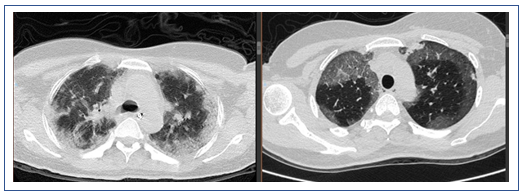

该患者急性起病,发热,痰中带血,病情较重,但影像学改变并不典型。患者胸部CT示双肺磨玻璃影,双下肺可以见与支气管伴行的肺血管明显增粗,右下肺可见血管影扩张,中叶胸膜下片状高密度影,左下肺血管影扩张较明显。目前在诊断方面考虑感染性病变和非感染性病变。非感染性病变主要考虑两类,一类是非肿瘤相关疾病,如自身免疫性疾病,另一类是肿瘤相关病变,如淋巴瘤、血液系统疾病等。结合患者的临床表现和检查结果,我个人认为非感染性疾病的可能性较大,仍需进一步检查明确,如支气管肺泡灌洗、肺活检等。

经过治疗后,该患者的氧合有所改善,胸部CT提示肺部磨玻璃影明显吸收,但斑片状实变影愈加明显。此外,还出现了少量的胸腔积液。所以还是考虑患者有无潜在的血管炎或结缔组织疾病。由于患者的血管病变比较突出,D-二聚体和肿瘤标志物水平升高。所以暂时不能除外淋巴瘤或血管相关肿瘤。此时可以考虑行支气管肺泡灌洗,同时取标本送病理检查。

该患者经过短期治疗后,肺部磨玻璃影明显吸收。这种效果应是来源于糖皮质激素的作用。除了血管炎是否也要考虑皮肌炎的可能,可以做皮肌炎抗体检查。另外,建议患者行支气管肺泡灌洗和NGS检查。患者胸部CT显示双下肺背段有斑片影,这或许与患者机械通气时间长有关,可能为重力依赖区斑片渗出影。